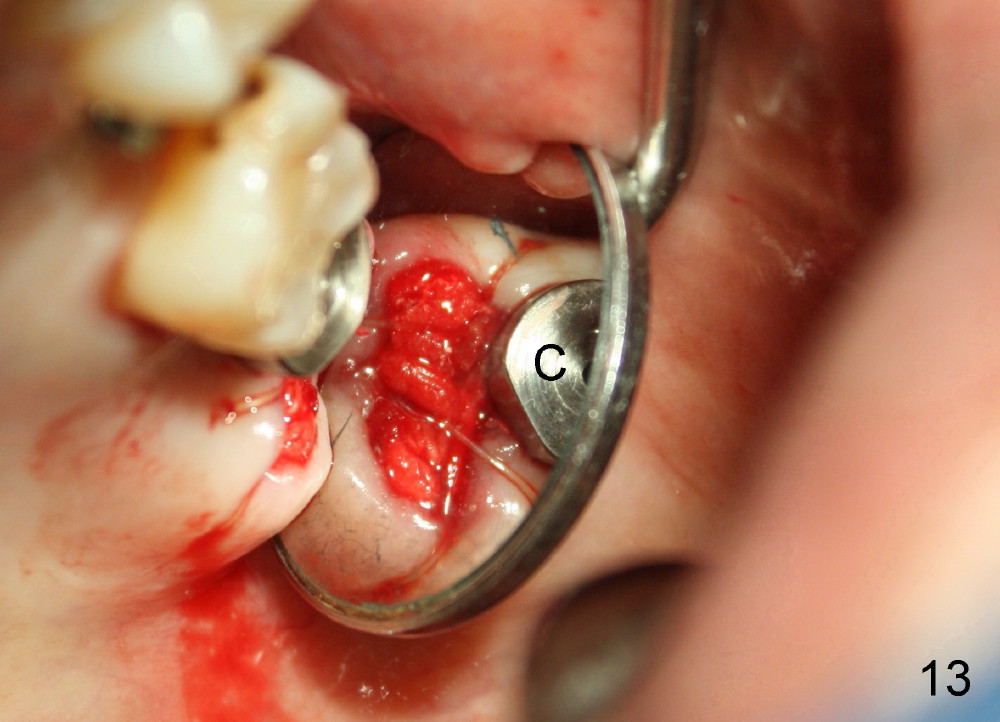

Postop, the patient has a car accident. She does not return for followup until 11 months later. The implant is stable. The neighboring third molar has caries (Fig.11 *). When it is extracted, the distal threads of the implant are found to be exposed (apical to ^ in Fig.12). A synthetic bone graft is placed to cover the exposed threads, followed by insertion of a collagen plug (Fig.13).